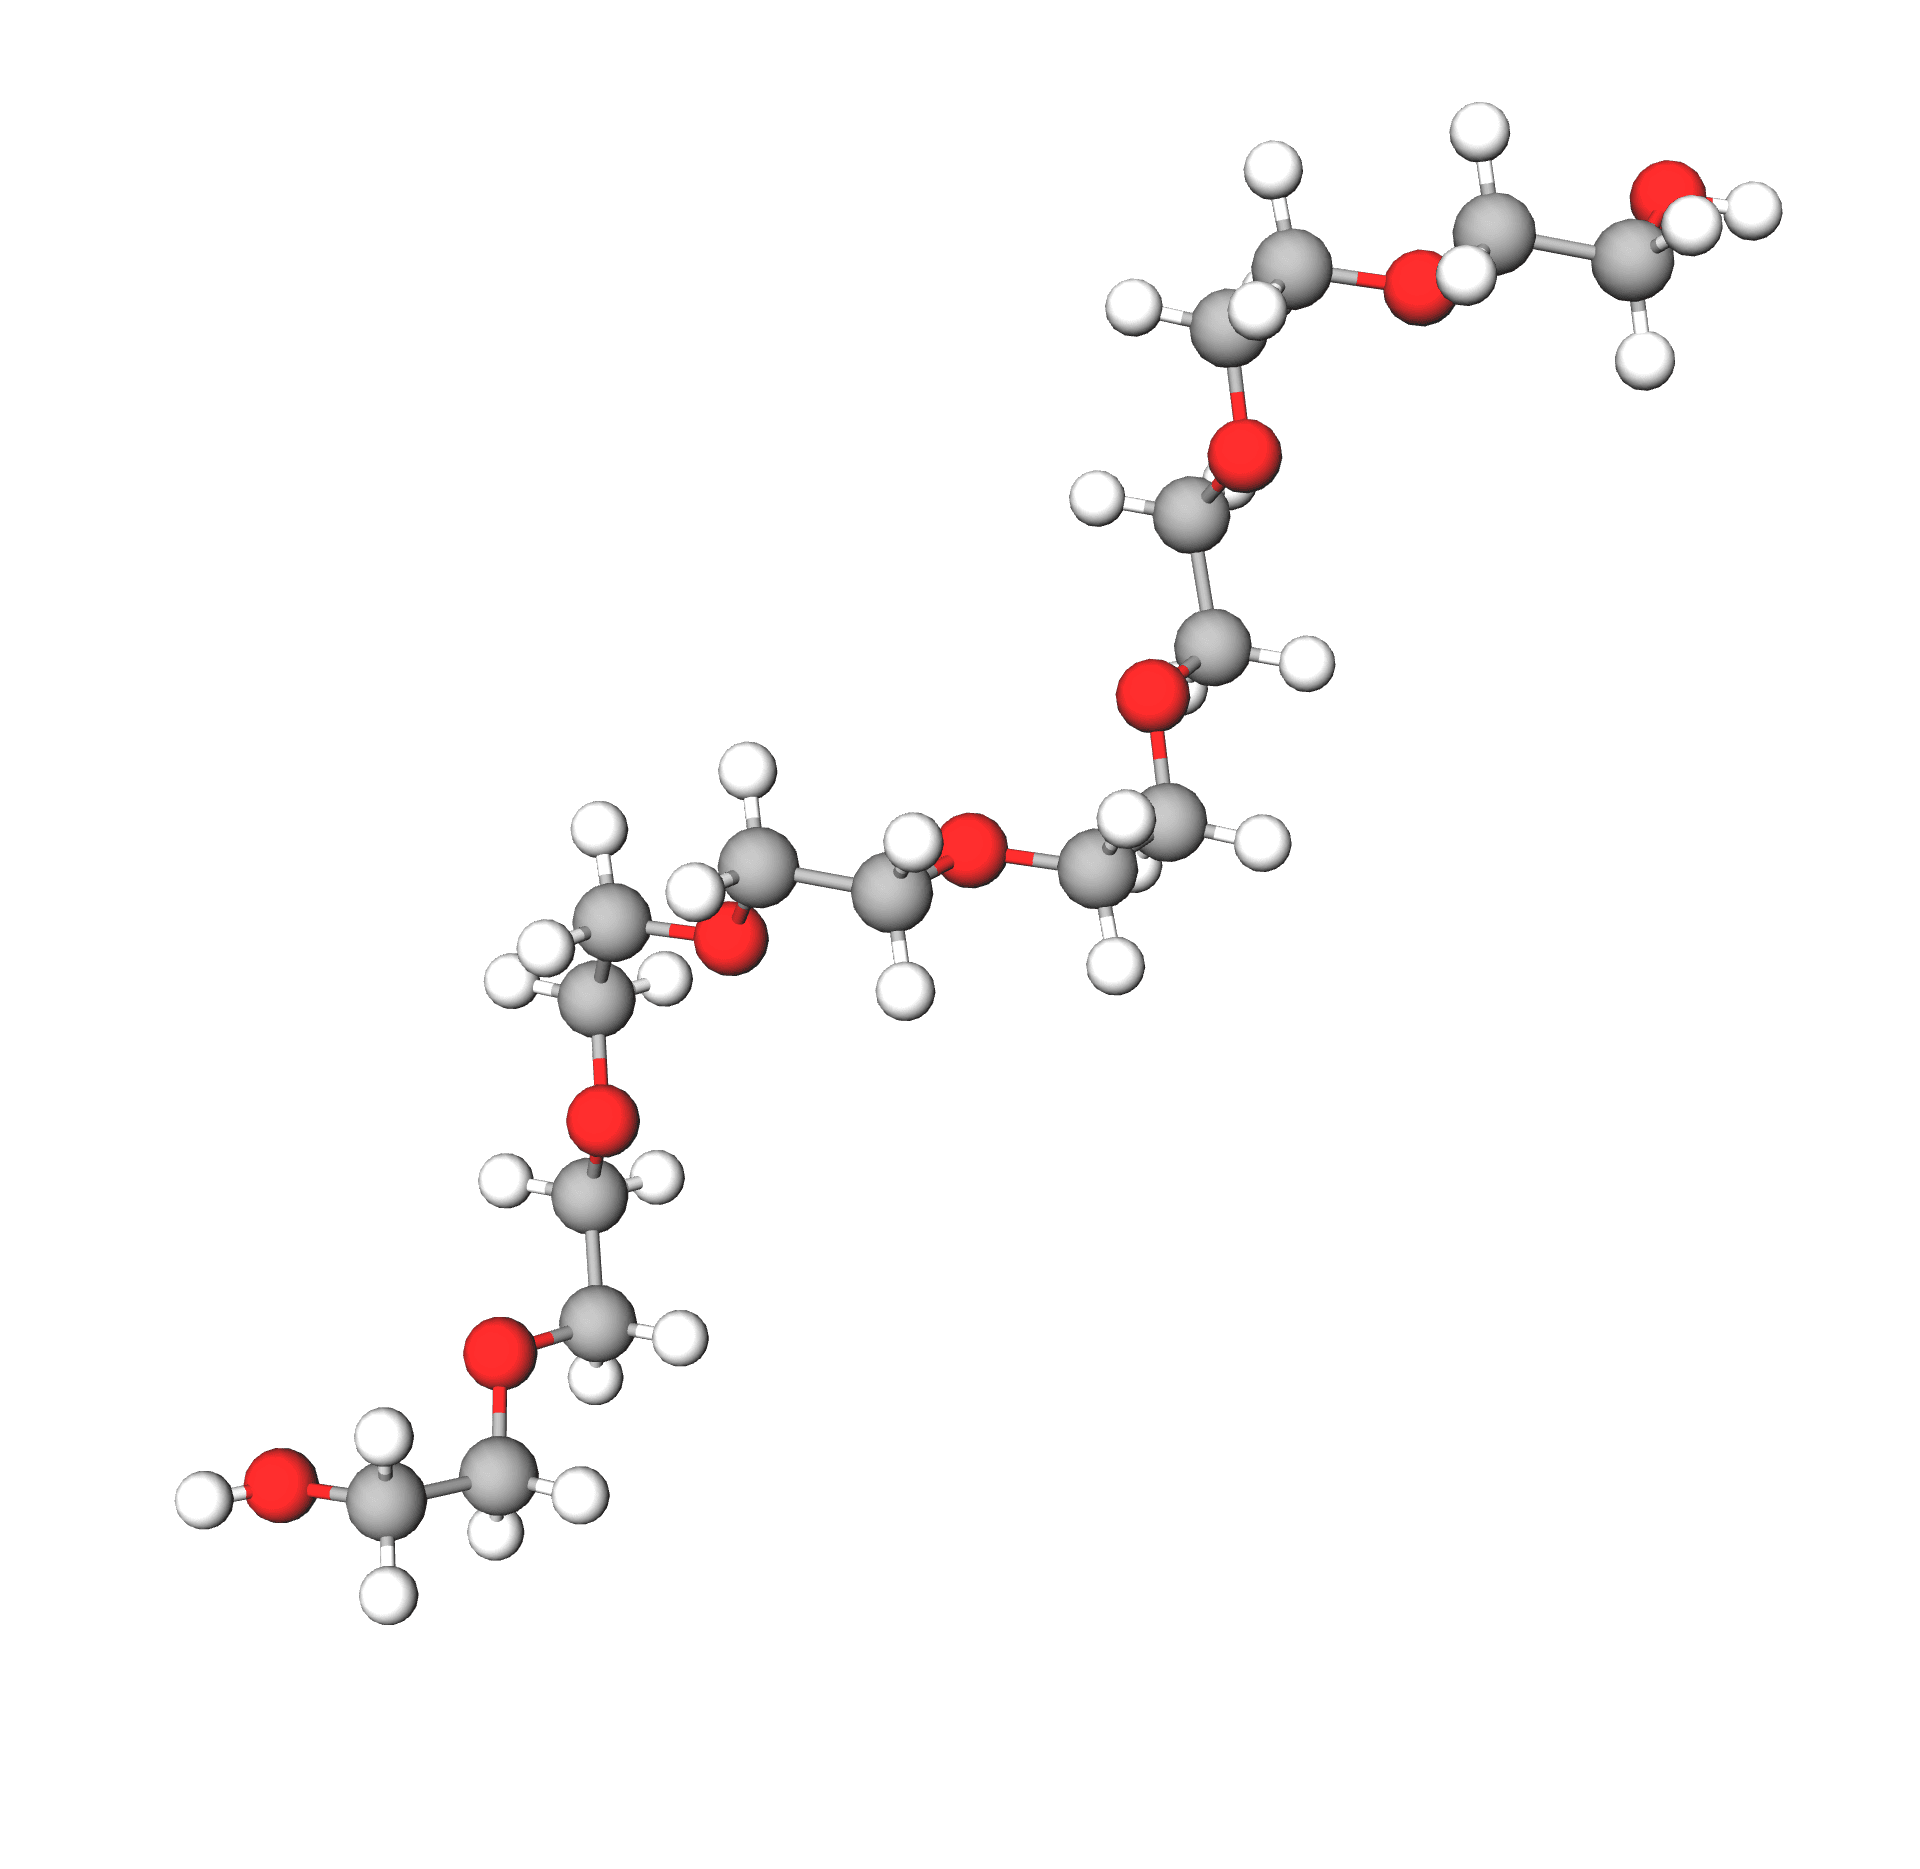

Poly Ethylene Glycol PEG Based Hydrogels For Drug Delivery In Cancer

Poly thyl ne Glycol PEG Structure Chimique Les Formes De PEG Sont

Polyethylene Glycol PEG Concepts Applications And Side Effects

Une Photographie Illustrant L application Du Peg Au Poly thyl ne Glycol